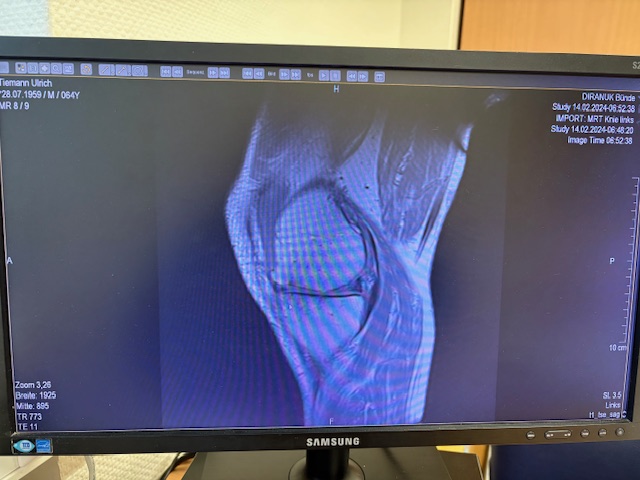

Ο ακτινολογικός έλεγχος (ακτινογραφίες/μαγνητική τομογραφία) ανέδειξε προχωρημένη οστεοαρθρίτιδα του έσω κονδύλου, με πλήρη διατήρηση του έξω διαμερίσματος και της επιγονατιδομηριαίας άρθρωσης. Με βάση αυτά τα ευρήματα, ο ασθενής ήταν ιδανικός υποψήφιος για μερική (μονοκονδυλική) αρθροπλαστική γόνατος.

Η ακριβής προσαρμογή του εμφυτεύματος επιβεβαιώθηκε διεγχειρητικά, εξασφαλίζοντας σταθερότητα και φυσική κίνηση της άρθρωσης.